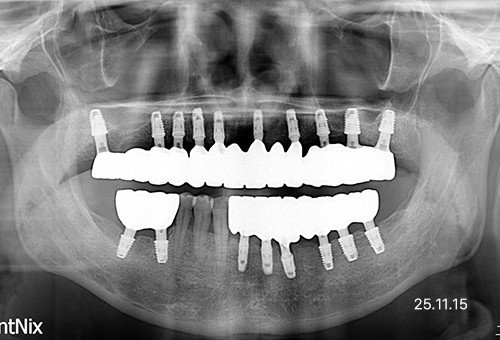

필요한 경우 발치 후 일정 기간 치유 상태를 확인한 뒤 임플란트를 진행하며, 치료 전 진단을 통해 건강보험 적용 여부를 확인하게 됩니다.

심한 충치나 치주질환으로 치아를 살리기 어려운 경우

자연치아를 보존하기 어려운 상태라면, 손상된 치아를 대신할 수 있는 임플란트 치료가 필요합니다.

사고 등으로 앞니나 어금니가 빠지거나 부러진 경우

출혈을 최소화한 안전한 시술을 원하시는 분에게 적합합니다.

주변 치아나 신경 손상이 걱정되시는 분

예기치 않은 외상으로 인해 치아가 손상되었을 경우, 심미성과 기능 회복을 위한 임플란트가 효과적인 치료 방법입니다